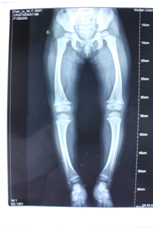

在女儿矫正期间,何女士又发现小儿子患有同样疾病,她不敢耽误,孩子1岁就带到武汉济世进行矫正治疗,经过武汉济世矫形专家们的精心设计、适配有效的矫形器,才短短一年时间,孩子就康复了,现在可以不用穿矫形器,像正常的儿童一样走路运动了。